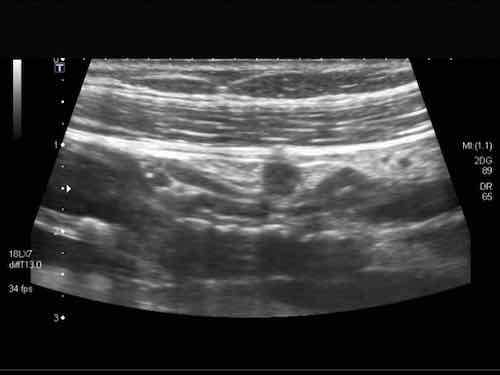

Intussusception

Đây là hình ảnh siêu âm của một trẻ 2 tuổi bị lồng ruột hồi manh tràng từng đợt, được khám trong khoảng thời gian giữa các cơn.

Hồi tràng với nhiều mảng Peyer sa vào manh tràng.

Hình ảnh siêu âm kinh điển của lồng ruột hồi-manh tràng ở hai trẻ khác nhau.

Trong cả hai trường hợp, đoạn hồi tràng bị lồng được định vị không đối xứng bên trong ống lồng ngoài, do mạc treo ruột tăng âm có chứa mỡ, bám vào hồi tràng và đi theo hồi tràng khi bị kéo vào trong.

Trong mạc treo, siêu âm cho thấy một hạch bạch huyết mạc treo (hbh) phóng đại ở cả hai.

Các hạch này phì đại như một phần của tình trạng tăng sản hạch bạch huyết toàn thân và khônghu trú trong lòng hồi tràng.

Do đó đây không phải là điểm dẫn đầu nguyên phát. Ở bệnh nhân bên phải, ruột thừa (mũi tên) cũng bị kéo vào trong.

Lưu ý cấu trúc đa lớp của thành bụng phía trước của phức hợp lồng ruột, đại diện cho ba lớp thành ruột bị gấp lại.